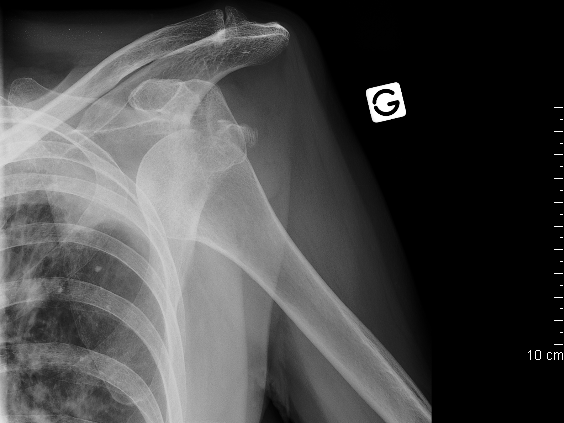

Eine Instabilität der Schulter kann sich in eine bestimmte Richtung entwickeln (nach vorne oder hinten) oder auch multidirektional sein, d.h. die Schulter ist in viele Richtungen instabil.

Eine unbehandelte Instabilität führt nicht nur zur Einschränkung der Lebensqualität, sondern kann auch langfristig eine Arthrose des Gelenkes zur Folge haben.